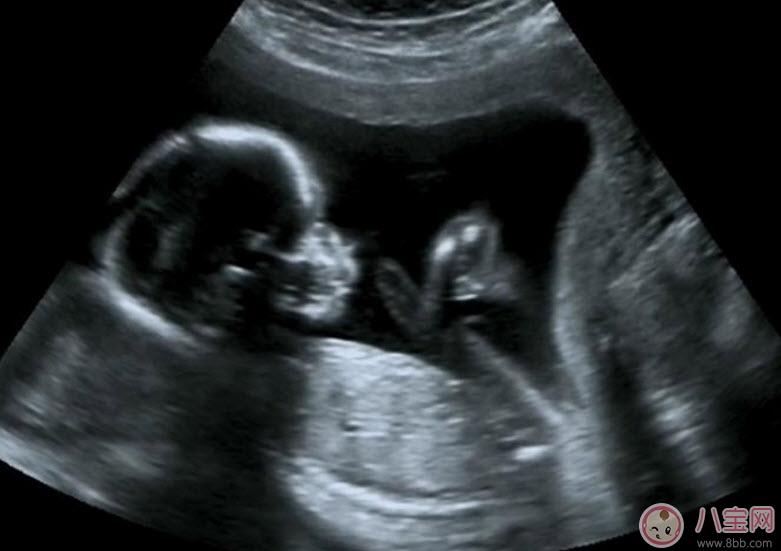

文章图片

B超能够直观胎儿在母体内的活动状况,诸如呼吸情况、胎儿的运动、整个身体大的运动、肢体的运动、胎儿的吞咽动作等等,可以一览无余 。之外,通过观察胎儿的张力是否良好,可以判断胎儿在宫内是否缺氧或者受到损害,准确预报胎儿安危 。